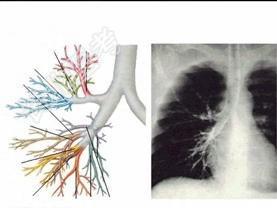

- 单项选择题右主支气管的特点见图 ( )

A、粗、短、垂直

B、短、细、垂直

C、短、细、倾斜

D、长、粗、倾斜

E、无上述特点